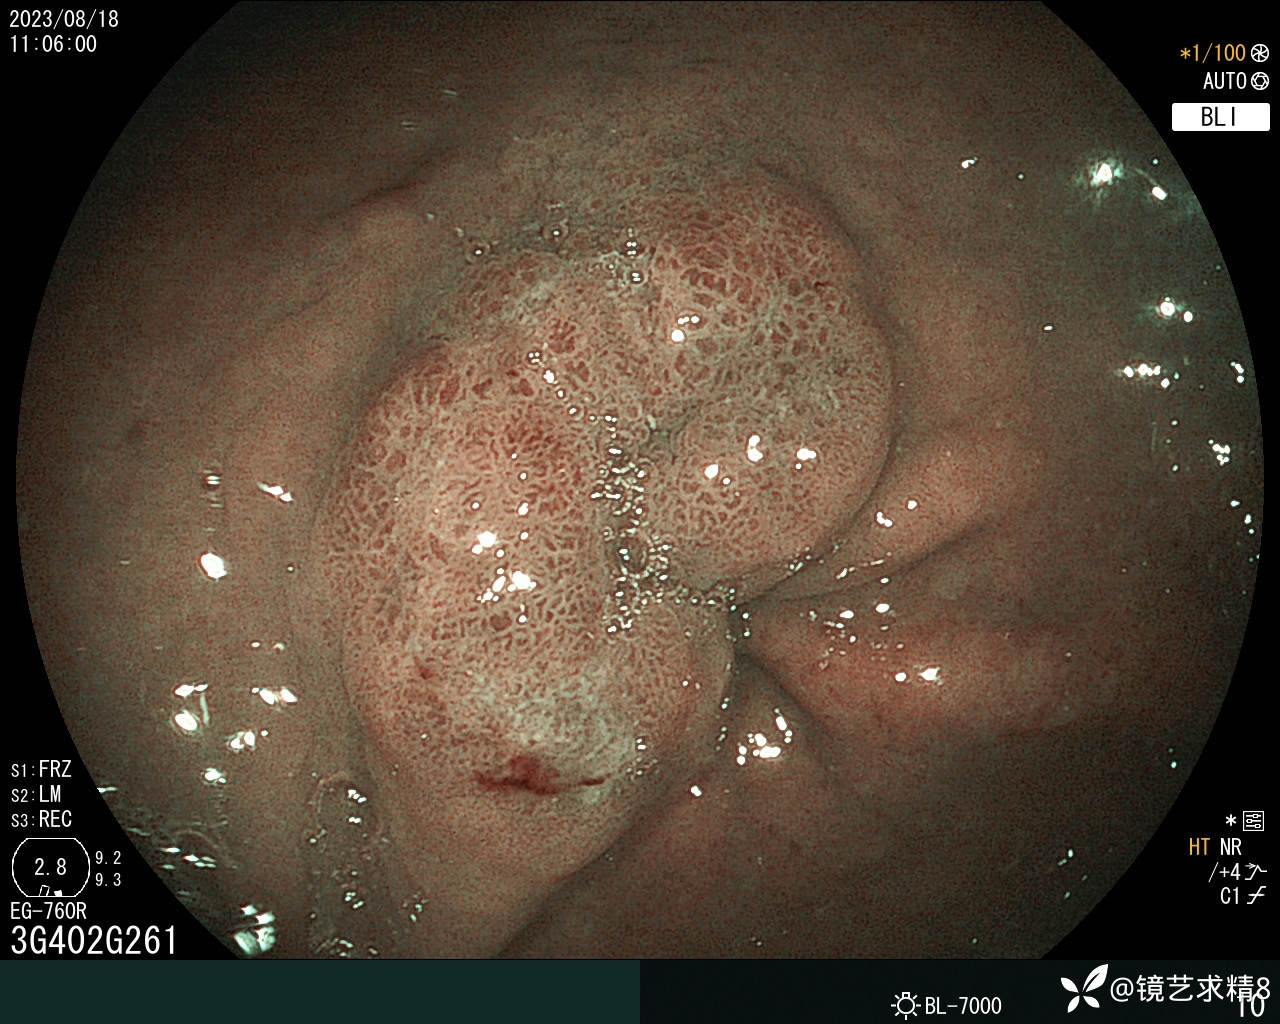

胃窦:黏膜红白相间,前壁与小弯侧交界近幽门见一0-Ia+IIc型病变,约20*30mm大小,BLI染色局部呈淡茶色,边界可见,表面结构欠规则,取病检2块+HP检查,质软。

内镜下诊断:1. 胃窦0-Ia+Ic型病变,不除外早期ca?请结合病检+HP检查